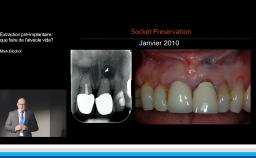

Cette conférence décrit la mise en œuvre d’un flux numérique dans le but de contribuer au respect des principes biologiques qui régissent le succès implant-prothétique. Le positionnement tridimensionnel du ou des implants est l’élément clé d’une bonne intégration tissulaire et esthétique. La possibilité d’anticiper ce positionnement lors d’une planification numérique par rapport aux tissus osseux, aux tissus mous et au projet prothétique est une plus-value importante. Autre avantage, la mise en charge et la temporisation immédiate sont plus ergonomiques. La technique est déclinée pour les édentements unitaires, pluraux, et complets.